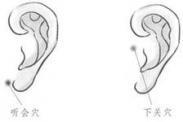

腎虛耳鳴

628健康網(wǎng)為您分享有關(guān)腎虛耳鳴的癥狀,腎虛耳鳴的治療方法,腎虛耳鳴的預(yù)防知識(shí),腎虛耳鳴的癥狀圖片,腎虛耳鳴吃什么藥,腎...